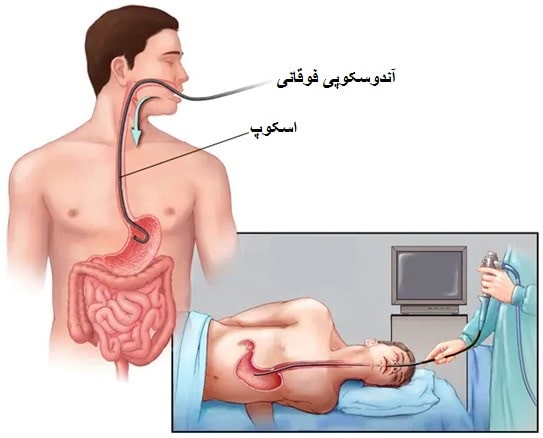

آندوسکوپی

خونریزی واریس مری یک مورد اورژانسی است که نیاز به درمان فوری دارد. بیمار در بیمارستان مقدار زیادی مایعات و خون دریافت میکند تا جایگزین خون از دست رفته شود. دو درمان مختلف غیرجراحی جهت توقف خونریزی واریس وجود دارد: لیگاسیون واریس که از طریق آندوسکوپ و شنت پورتوسیمتیک داخلی کبدی داخل جفتی (TIPS) توسط متخصص رادیولوژیست با تصویربرداری اشعه ایکس انجام میشود.

لیگاسیون واریس

- نقاط قرمز روی واریس مری که با آندوسکوپی شکم مشاهده میشود.